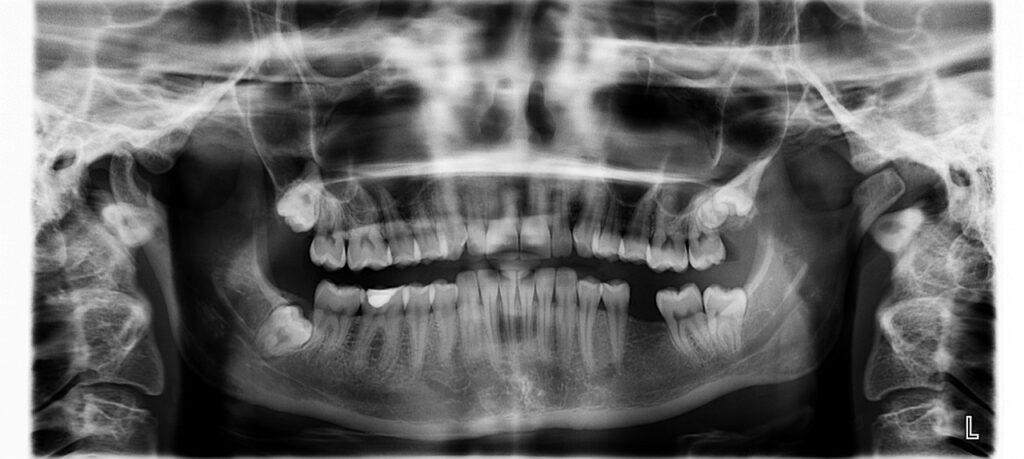

مش كل مشكلة في الأسنان بتبان بالعين، وعشان كده الأشعة الرقمية عندنا بتكون أول خطوة للتشخيص الدقيق. في Smiley Dental Care، الأشعة متوفرة داخل العيادة مجاناً ضمن زيارتك — بأحدث الأجهزة اللي بتوضح التفاصيل بوضوح، وبتساعدنا نحدد السبب الحقيقي ونعالج من أول مرة.

إمتى أحتاج أشعة أسنان؟

ألم في السن ومش واضح السبب.

علاج عصب أو تركيب.

شك في وجود تسوس داخلي أو خُراج.

تقويم أو خلع ضرس عقل.